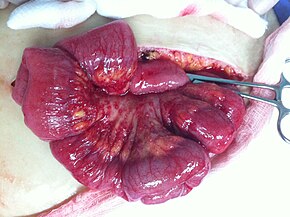

To definitively diagnose ovarian cancer, a surgical procedure to inspect the abdomen is required. This can be an open procedure (laparotomy, incision through the abdominal wall) or keyhole surgery (laparoscopy). During this procedure, suspicious tissue is removed and sent for microscopic analysis. Usually, this includes a unilateral salpingo-oophorectomy, removal of a single affected ovary and Fallopian tube. Fluid from the abdominal cavity can also be analyzed for cancerous cells. If cancer is found, this procedure can also be used to determine the extent of its spread (which is a form of tumor staging).[19]

Surgery has been the standard of care for decades and may be necessary in obtaining a specimen for diagnosis. The surgery depends upon the extent of nearby invasion of other tissues by the cancer when it is diagnosed. This extent of the cancer is described by assigning it a stage, the presumed type, and the grade of cancer. The gynecological surgeon may remove one (unilateral oophorectomy) or both ovaries (bilateral oophorectomy). The Fallopian tubes (salpingectomy), uterus (hysterectomy), and the omentum (omentectomy) may also be removed. Typically, all of these organs are removed.[61]

In advanced cancers, where complete removal is not an option, as much tumor as possible is removed in a procedure called debulking surgery. This surgery is not always successful, and is less likely to be successful in women with extensive metastases in the peritoneum, stage- IV disease, cancer in the transverse fissure of the liver, mesentery, or diaphragm, and large areas of ascites. Debulking surgery is usually only done once.[21] Computed tomography (abdominal CT) is often used to assess if primary debulking surgery is possible, but low certainty evidence also suggests fluorodeoxyglucose‐18 (FDG) PET/CT and MRI may be useful as an addition for assessing macroscopic incomplete debulking.[63] More complete debulking is associated with better outcomes: women with no macroscopic evidence of disease after debulking have a median survival of 39 months, as opposed to 17 months with less complete surgery.[19] By removing metastases, many cells that are resistant to chemotherapy are removed, and any clumps of cells that have died are also removed. This allows chemotherapy to better reach the remaining cancer cells, which are more likely to be fast-growing and therefore chemosensitive.[22]

There are several different surgical procedures that can be employed to treat ovarian cancer. For stage I and II cancer, laparascopic (keyhole) surgery can be used, but metastases may not be found. For advanced cancer, laparoscopy is not used, since debulking metastases requires access to the entire peritoneal cavity. Depending on the extent of the cancer, procedures may include a bilateral salpingo-oophorectomy, biopsies throughout the peritoneum and abdominal lymphatic system, omentectomy, splenectomy, bowel resection, diaphragm stripping or resection, appendectomy, or even a posterior pelvic exenteration.[22]